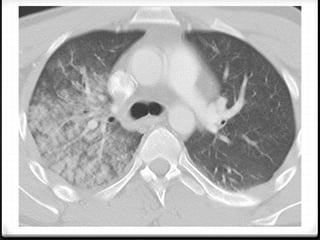

0 Kontusio paru

0 Cedera paling sering pada parenkim paru bila terjadi trauma

thoraks dengan prevalensi 17%–70%

0 Kontusio  cedera alveoli tanpa disrupsi

0 Muncul ketika terjadi trauma dan berada di lokasi trauma,

countercoup masih mungkin terjadi

0 Radiografi polos bisa mendiagnosis namun CT scan memiliki

sensitivitas lebih tinggi.

0 Radiografi  sekitar 6 jam

0 CT scan segera setelah trauma

0 Resolusi kontusio terjadi dalam waktu 1-2 hari dan hilang

sempurna dalam waktu 3-10 hari

0 Bila muncul area fokal lebih dari 24 jam  bukan kontusio

0 Cedera palingsering pada parenkim paru bila terjadi trauma thoraks dengan prevalensi 17%–70% 0 Kontusio  cedera alveoli tanpa disrupsi 0 Muncul ketika terjadi trauma dan berada di lokasi trauma, countercoup masih mungkin terjadi 0 Radiografi polos bisa mendiagnosis namun CT scan memiliki sensitivitas lebih tinggi. 0 Radiografi  sekitar 6 jam 0 CT scan segera setelah trauma 0 Resolusi kontusio terjadi dalam waktu 1-2 hari dan hilang sempurna dalam waktu 3-10 hari 0 Bila muncul area fokal lebih dari 24 jam  bukan kontusio